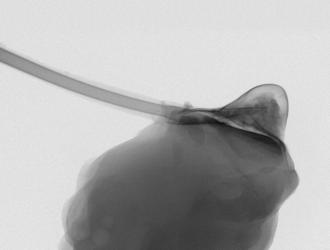

ArrivaTherepi”, un microscopico serbatoio di farmaci che si attacca direttamente al cuore e che può essere riempito dall'esterno in modo semplice grazie a un “tubicino” di collegamento che finisce sotto cute.

Therepi rilascia farmaci in modo controllato e localizzato per...